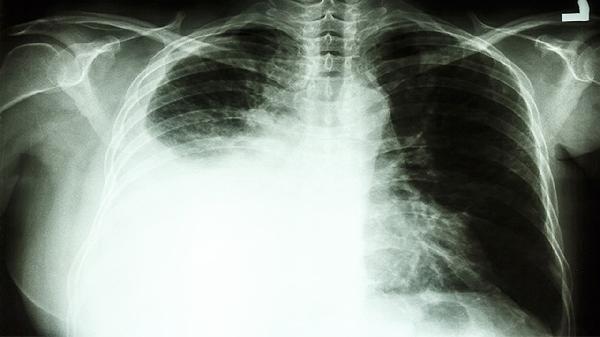

当CT报告上"肺腺癌晚期"几个字刺入眼帘时,诊室里的空气瞬间凝固。51岁的老周攥着检查单的手不停发抖,女儿蹲在墙角掩面痛哭——这个场景肿瘤科医生见过太多次。令人扼腕的是,三个月前体检时医生就反复提醒他"肺部磨玻璃结节有恶变风险",可那句"我抽烟三十年都没事"的侥幸,最终酿成了无法挽回的结局。

1、低剂量螺旋CT

能发现0.5cm的微小结节,辐射量仅为常规CT的1/6。建议40岁以上吸烟者每年做一次。